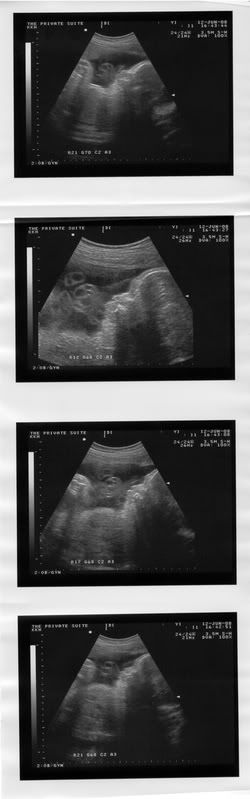

34 weeks now!!

Princess Cupcake!!!

I swear my gynae loves to pamper me with pics of her..4 pics, this time!!